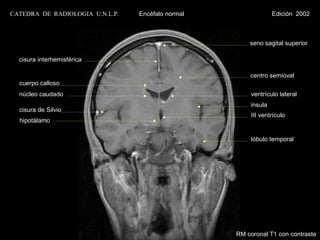

CATEDRA DE RADIOLOGIA U.N.L.P.   Encéfalo normal                Edición 2002

seno sagital superior

cisura interhemisférica

centro semioval

cuerpo calloso

núcleo caudado                                        ventrículo lateral

ínsula

cisura de Silvio

III ventrículo

hipotálamo

lóbulo temporal

RM coronal T1 con contraste